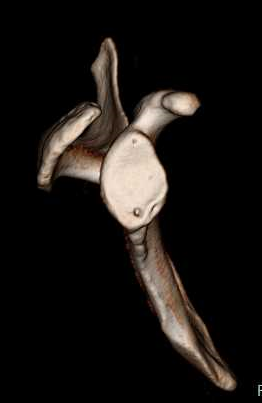

CT撮影

CT検査(Computed Tomography:コンピュータ断層診断装置) CT検査は、X線を使って身体の断面を撮影する検査です。骨折の部位の特定、転位(骨のずれ方)など判断できます。